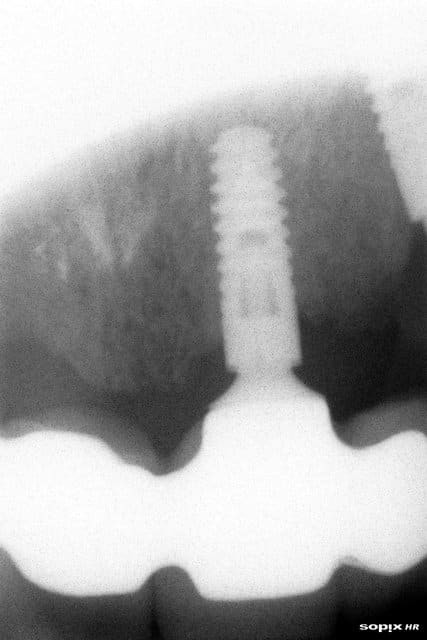

Je ne fais pas d'implanto, mais au regard de la Rx, mon vieil instinct de matou me dit que c'est trop fin, que la couronne est trop haute, que l'etraglement est trop important.

Y'avait l'air d'avoir de la place, non? pourquoi dans ce cas ne pas prendre des dimensions qui ressembloent a celles d'une racine de premo???

oui, mais le problème n'est pas dans le sens mésio distal...plus certainement en vestibulo palatin...

m'est d'avis qu'un petite expansion aurait permis de placer un 3.75 au lieu d'un 3.3...mais çà n'enlève pas le problème de growly qui a eu le même problème sur cet implant standard de 3.75...

Parce que des fois en VD on n'a pas la place, j'aurais pu faire de l'expansion c'est sûr, j'aime bien en plus mais c'était une extrac imp immédiate, pas osé.

Je pense quand même qu'en alliage de titane ça n'aurait pas cassé, reste à savoir si le design de l'implant, et les microspires ne fragilisent pas trop.

Un autre design dans ce diamètre, et an alliage n'aurait pas cassé je pense.